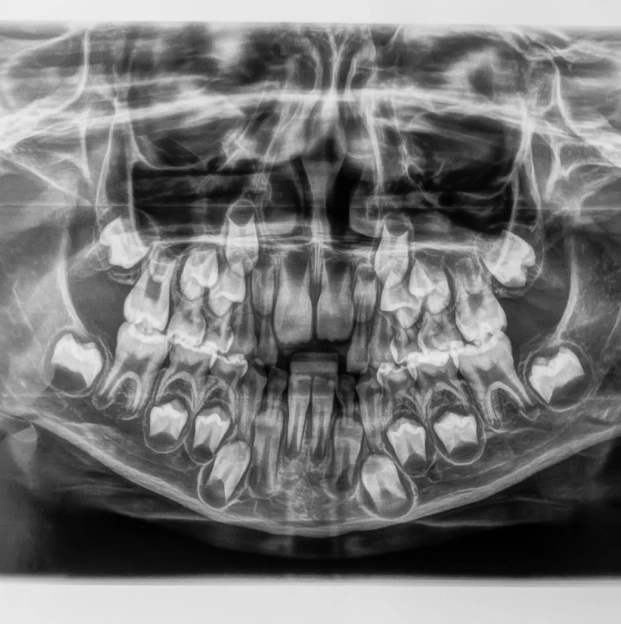

A Panorex is a highly advanced imaging tool that offers a comprehensive view of your dental and skeletal structure, far beyond what a standard X-ray can provide. During the procedure, you'll sit comfortably with your chin resting on a small ledge. The machine then rotates around your head, capturing a full 360-degree image of your teeth, sinuses, and bone structure.

This panoramic view is invaluable for your dentist, as it helps in detecting a wide range of issues, including structural problems, infections, and asymmetries. By examining the complete structure of your head, we can ensure that everything is functioning correctly and address any potential concerns.